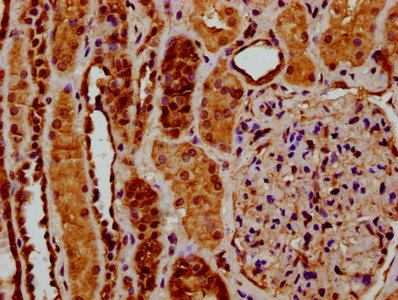

IHC image of CSB-PA020617LA01HU diluted at 1:200 and staining in paraffin-embedded human kidney tissue performed on a Leica BondTM system. After dewaxing and hydration, antigen retrieval was mediated by high pressure in a citrate buffer (pH 6.0). Section was blocked with 10% normal goat serum 30min at RT. Then primary antibody (1% BSA) was incubated at 4°C overnight. The primary is detected by a biotinylated secondary antibody and visualized using an HRP conjugated SP system.

IHC image of CSB-PA020617LA01HU diluted at 1:200 and staining in paraffin-embedded human breast cancer performed on a Leica BondTM system. After dewaxing and hydration, antigen retrieval was mediated by high pressure in a citrate buffer (pH 6.0). Section was blocked with 10% normal goat serum 30min at RT. Then primary antibody (1% BSA) was incubated at 4°C overnight. The primary is detected by a biotinylated secondary antibody and visualized using an HRP conjugated SP system.